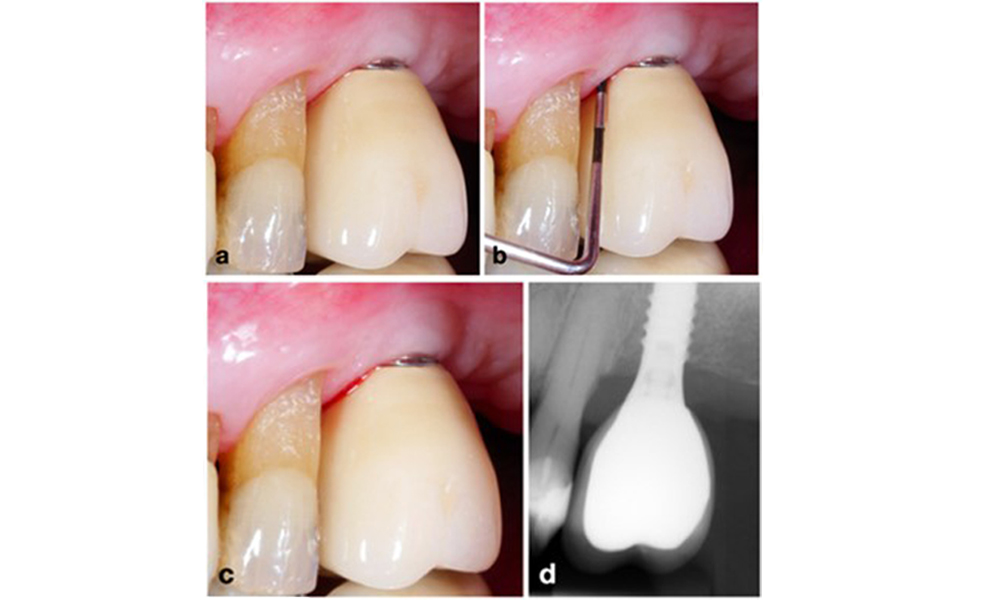

The prosthetic restoration should be removed during both non-surgical and surgical treatment to improve access to the implant surface. The choice of surgical intervention (e.g., resective, reconstructive, or combined) depends on several factors: (1) defect morphology (e.g., horizontal, dehiscence, intra-osseous, or combined) (figure 10), (2) implant surface (i.e., turned or modified/”rough”), and (3) presence or absence of sufficient keratinised and attached mucosa.

Defect morphology is one of the parameters defining the type of surgical intervention. While circumferential intrabony defects (a) can be treated well with a reconstructive approach, primarily horizontal bone defects (b) require a more resective approach.

Figure 10. Defect morphology is one of the parameters defining the type of surgical intervention. While circumferential intrabony defects (a) can be treated well with a reconstructive approach, primarily horizontal bone defects (b) require a more resective approach.

A resective approach (i.e., gingivectomy and/or apically positioned flap, with/without bone re-contouring) should be chosen in cases with mainly horizontal bone loss or wide defects, where the potential for bone regeneration is limited (figure 11).

Patient treated with a resective approach (a). After flap elevation mainly horizontal bone loss is seen (b), addressed by bone re-contouring (c) and an apically displaced flap resulting in a stable post-operative result (d).

Figure 11. Patient treated with a resective approach (a). After flap elevation mainly horizontal bone loss is seen (b), addressed by bone re-contouring (c) and an apically displaced flap resulting in a stable post-operative result (d).

For implants with a modified surface and in regions where bone regeneration is unlikely, implantoplasty should be considered. This procedure involves removing implant threads and smoothing of the micro-structured implant surface with rotating instruments (figure 12). This approach facilitates comprehensive decontamination of the implant surface, and – most importantly – improves postoperative biofilm control (Bertl and Stavropoulus 2021; El Chaar et al. 2020; Geremias et al. 2017). Due to a lack of sufficient clinical evidence there is controversy about the role of implantoplasty (Herrera et al. 2023; Ramanauskaite et al. 2021), however the concerns about inducing inflammation by the inevitable deposition of titanium particles and the increased risk of implant fracture due to reduction of implant strength have not been substantiated (Stavropoulos et al. 2019).

For implants with a modified surface in areas where bone regeneration is limited, implantoplasty should be considered. In a case with a buccal dehiscence, the buccal aspect of the modified implant surface (a) underwent implantoplasty (b–d), with surrounding tissues covered to minimise contamination from titanium particles, using gauze and liquid rubber dam.

Figure 12. For implants with a modified surface in areas where bone regeneration is limited, implantoplasty should be considered. In a case with a buccal dehiscence, the buccal aspect of the modified implant surface (a) underwent implantoplasty (b–d), with surrounding tissues covered to minimise contamination from titanium particles, using gauze and liquid rubber dam.

An implant harbouring a primarily circumferential intrabony defect (a) should be treated with a reconstructive approach. For grafting, autologous bone was collected with a piezo surgery device (b-c) and the defect was covered with a collagen membrane (d).

Figure 13. An implant harbouring a primarily circumferential intrabony defect (a) should be treated with a reconstructive approach. For grafting, autologous bone was collected with a piezo surgery device (b-c) and the defect was covered with a collagen membrane (d).

A reconstructive approach is recommended for implants with modified surfaces and intra-osseous defects, where the potential for re-osseointegration is much higher (Monje et al. 2023; Renvert et al. 2009). This may encompass the utilisation of autogenous bone, bone substitutes, and/or membranes (figure 13) (Donos et al. 2023). Certainly, a reconstructive approach necessitates thorough decontamination of the implant surface. Both laboratory and preclinical studies indicate the impracticality of achieving complete biofilm removal from the implant surface (Subramani & Wismeijer 2012). Therefore, it is recommended to employ a combination of mechanical and chemical measures for effective decontamination, although no specific method can be considered as superior (Ramanauskaite et al. 2023; Wilensky et al. 2023). Air-polishing devices have demonstrated superior efficacy in biofilm removal based on several laboratory studies (Francis et al. 2022; Keim et al. 2019, Sahrmann et al., 2015). However, it is important to note that the intra-operative use of air-polishing is considered off-label.